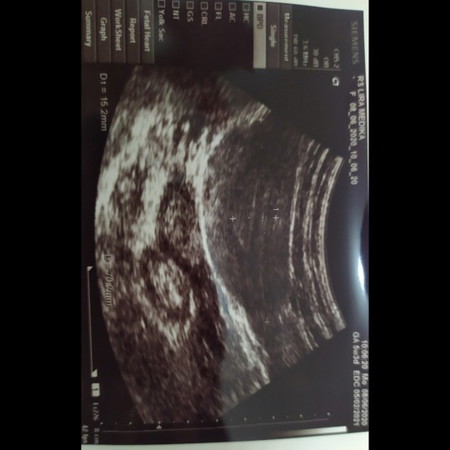

Belum ada kantong, itu hamil belum?

Tadi pagi tespeck ternyata positif, terus langsung ke dokter katanya baru penebalan rahim belum ada kantongnya, berarti hamil atau engga?